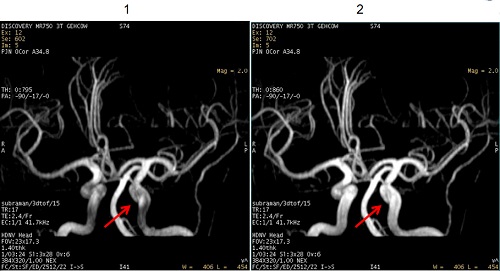

| 1 | Fat enhancement = 0. |

| 2 | Fat enhancement = 1, note the improved vessel signal. |